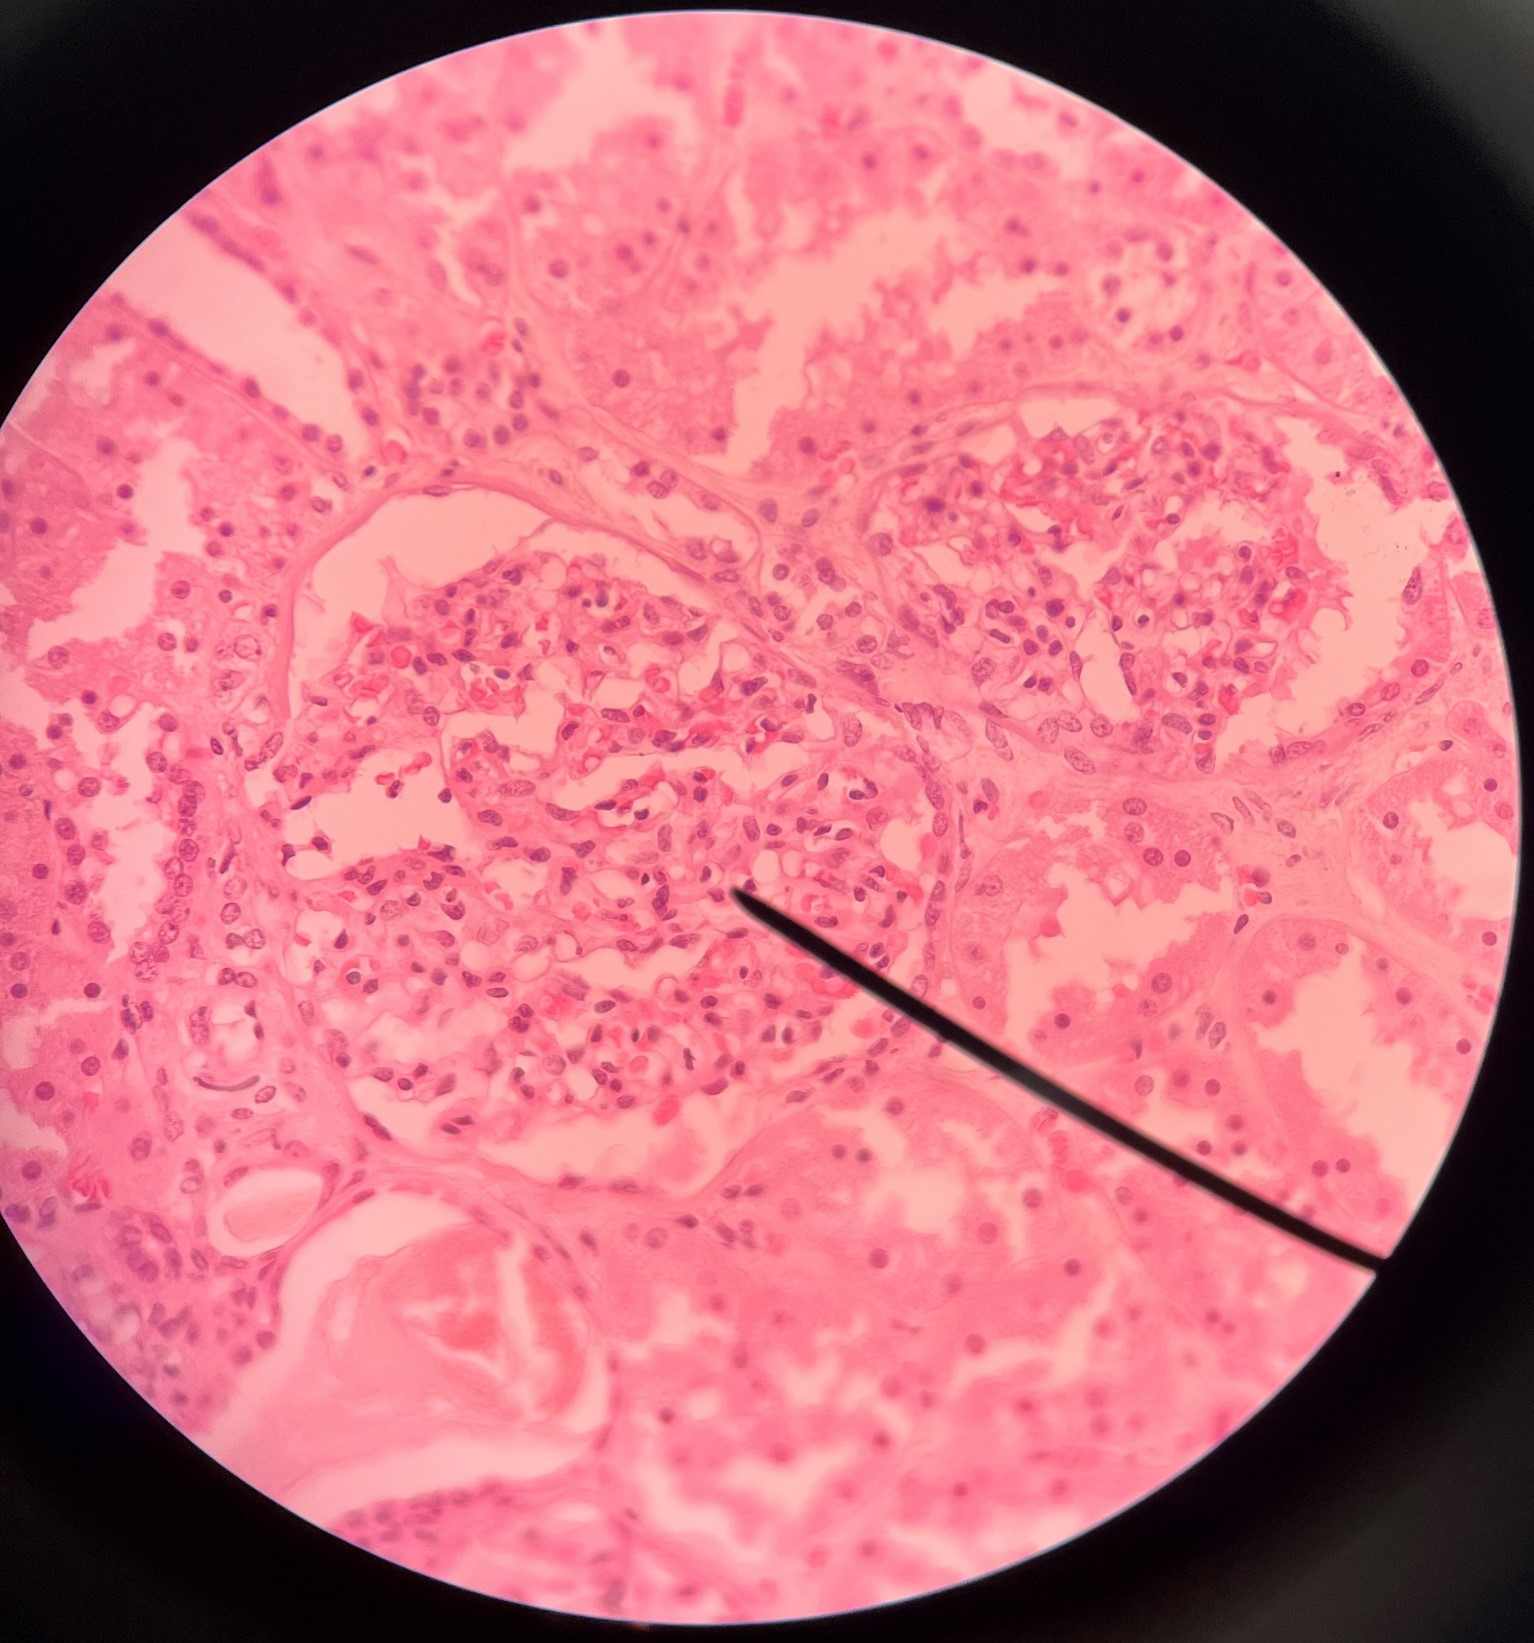

nephron

• The functional subunit of the kidney.

• Site of urine formation and renal function.

• Composed of a renal corpuscle and a renal tubule.

renal corpuscle

• Part of a nephron.

• Filters blood.

• Composed of a glomerulus enclosed within a glomerular capsule.

glomerulus

• Slide histology of the nephron.

• Part of a renal corpuscle.

• The capillary network of a renal corpuscle.

capsular space

• Slide histology of the nephron.

• Part of a renal corpuscle.

• The interior of the glomerular capsule.

glomerular capsule

• Slide histology of the nephron.

• Part of a renal corpuscle.

• A wall enclosing the glomerulus.

• Shown in the image is the parietal layer.

podocyte

• Part of a renal corpuscle.

• A cell with pedicels.

• Wraps around the glomerulus and forms the visceral layer of the glomerular capsule.

renal tubule

• Slide histology of the nephron.

• Part of a nephron.

• Modifies glomerular filtrate by reabsorption and secretion of water and ions.

• Divided into the proximal convoluted tubule, loop of Henle, and distal convoluted tubule.

proximal convoluted tubule

• The first part of a renal tubule.

• Primary site of water and solute reabsorption.

• Begins immediately after the renal corpuscle.

• Abbreviated PCT.

distal convoluted tubule

• The third part of a renal tubule.

• Primary site of secretion of excess solutes.

• Abbreviated DCT.

collecting duct

• The convergence of several distal convoluted tubules.

• Descends through the renal pyramid.

• Merges with others to form larger papillary ducts that drain into the minor calyces.

• Abbreviated CD.

afferent arteriole

• Branches of an interlobular artery.

• Supplies the glomerulus of a nephron for blood filtration.

efferent arteriole

Vessel carrying blood away from the glomerulus to the peritubular capillaries.

peritubular capillaries

• Branches of an efferent arteriole.

• Supplies the adjacent renal tubules in the renal cortex.

vasa recta

• Branches of an efferent arteriole.

• Supplies the loops of Henle in the renal medulla.